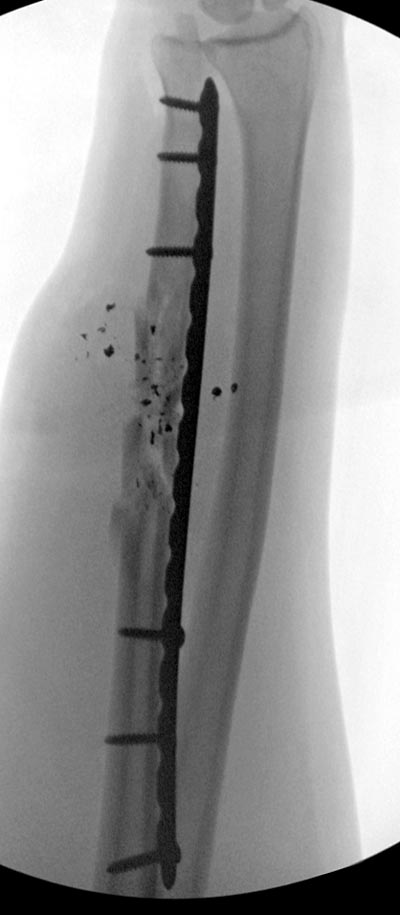

Здесь примеры: двоюродные братья с ранением предплечья, у одного

локтевая, а у второго лучевая. В следующее утро локтевая фиксирована без

обнажения фокуса травмы из небольших доступов, а второй из обычного

волярного доступа. А клинический снимок из прошлых операций...

Вложение не в текстовом формате было извлечено…

Имя     : GSW radius 2.jpg

Тип     : image/jpeg

Размер  : 33680 байтов

Url     : http://weborto.net:8080/pipermail/ortho/attachments/20140728/123f732a/attachment-0011.jpg